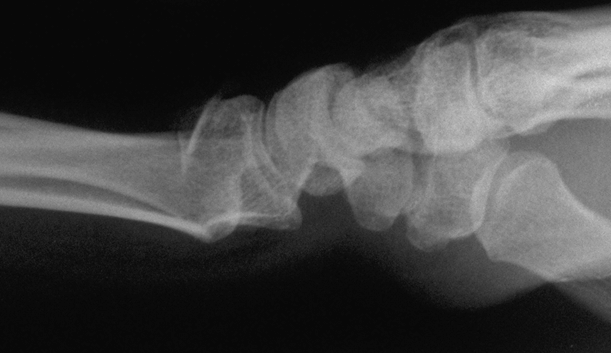

Case 3 Preop

Case3 Preop